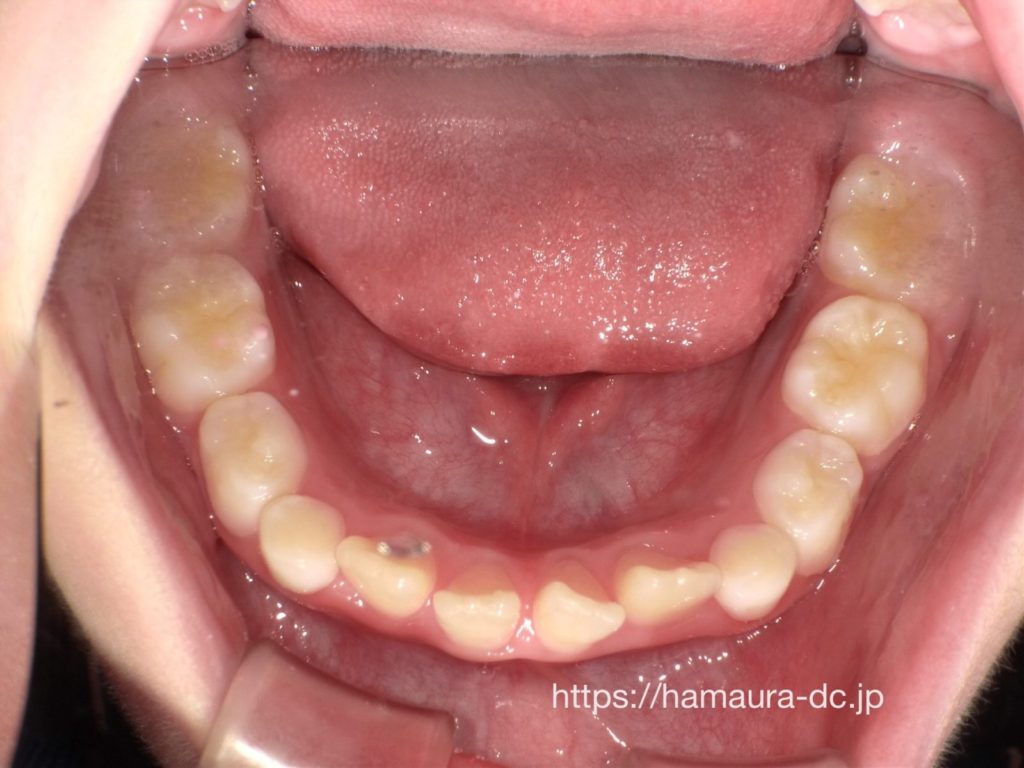

治療後

顎を広げることで

👉 前歯の重なりが改善し

👉 歯が並ぶスペースが確保されました

現在は安定した歯並びを維持しています

治療期間について

この症例では

👉 7歳から治療を開始し、約3年で改善しました